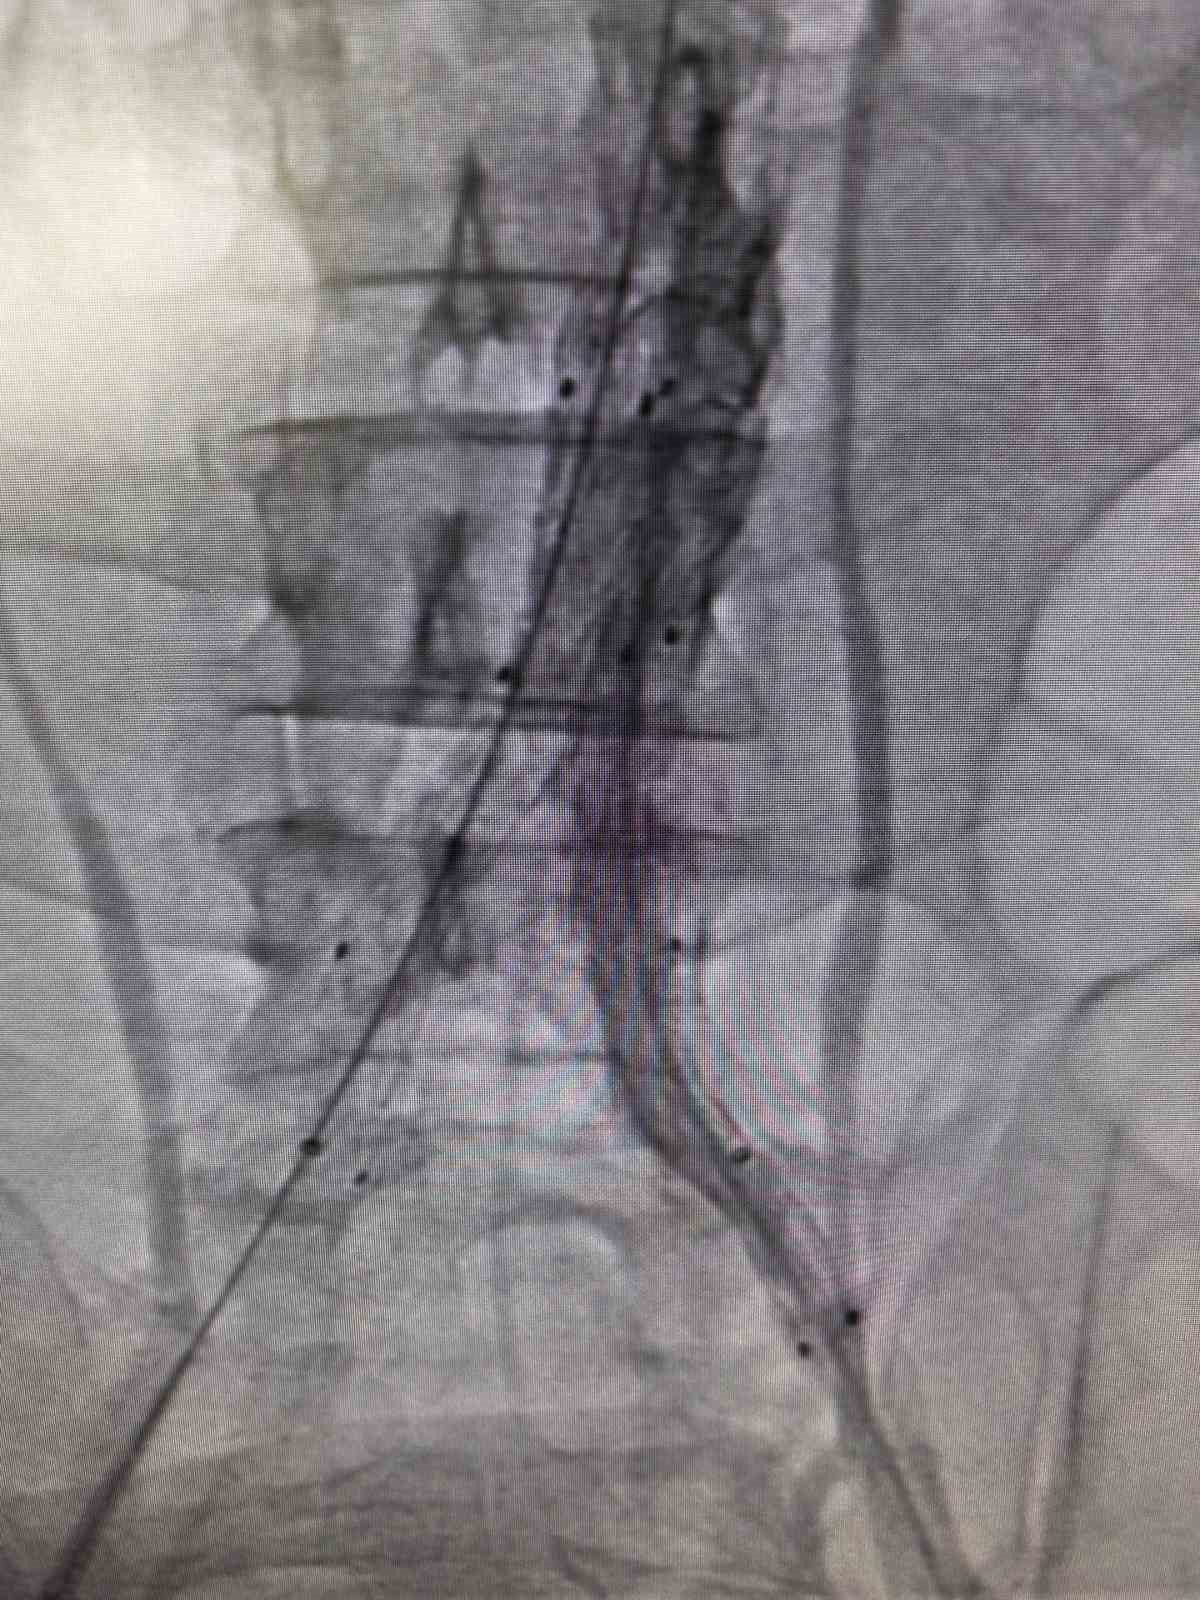

Bilecik Eğitim ve Araştırma Hastanesi’nde daha önce farklı sağlık kuruluşlarına başvuran ancak net bir tanı konulamayan hasta, acil servisinde yapılan detaylı tetkikler sayesinde doğru tanıya ulaştırıldı. Şiddetli sırt ve karın ağrısı şikâyetiyle hastaneye başvuran 39 yaşındaki Mehmet D.’nin acil serviste çekilen ileri görüntüleme tetkiklerinde, kalpten çıkan ana damarın iç duvarında yırtılma olduğu belirlendi. Hayati risk taşıyan bu durum üzerine hasta, kalp ve damar cerrahisi ekibi tarafından acil olarak değerlendirmeye alındı.Hasta, Kalp ve Damar Cerrahisi Uzmanı Op. Dr. Elmas Üreyen tarafından kapalı yöntemle tedavi edildi. Damar içinden girilerek yapılan işlem sırasında, yırtılan ana damarın içine özel bir stent yerleştirildi ve damar içten onarıldı. Açık ameliyata gerek kalmadan gerçekleştirilen bu yöntem sayesinde hasta kısa sürede rahatladı.Tedavi sonrası yakından takip edilen hastanın ağrılarının tamamen geçtiği, genel sağlık durumunun iyi olduğu gözlemlendi. Kontrollerinin sorunsuz seyretmesi üzerine hasta sağlıklı bir şekilde taburcu edildi.

Konuyla ilgili açıklama yapan Op. Dr. Elmas Üreyen, "Bu tür damar yırtılmaları ani gelişebilen ve zamanında müdahale edilmezse hayati risk taşıyan durumlardır. Hastamızda erken tanı koyarak kapalı yöntemle müdahale ettik. Açık ameliyata gerek kalmadan yapılan bu işlem, hastanın hem daha hızlı iyileşmesini hem de günlük yaşamına kısa sürede dönmesini sağladı. Hastanemizde, ileri teknoloji tıbbi cihazlar ve deneyimli hekim kadrosu ile bu tür yüksek riskli damar hastalıklarının tanı ve tedavisi başarıyla gerçekleştirilmektedir. Kapalı yöntemlerle uygulanan bu tedaviler, hastalara daha konforlu bir süreç sunarken, iyileşme süresini de önemli ölçüde kısaltmaktadır" dedi.